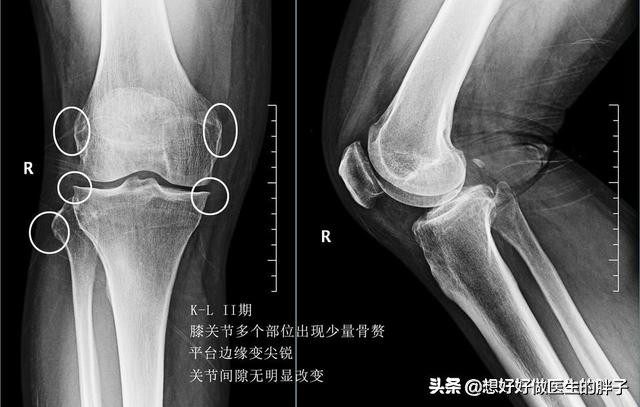

早期的患者往往是有膝关节的僵硬感,尤其是在早晨的时候比较明显,而且在体位改变的时候会有明显的启动疼痛,比如久坐之后站起来会有关节的疼痛,活动一会儿之后症状消失了。这些患者会表现为在上、下楼梯的时候关节疼痛,在走路的时候往往并没有什么太特殊的症状。而去医院进行膝关节x线检查,往往可以看到关节内有少量的骨赘形成,但是关节间隙并没有明显的狭窄。